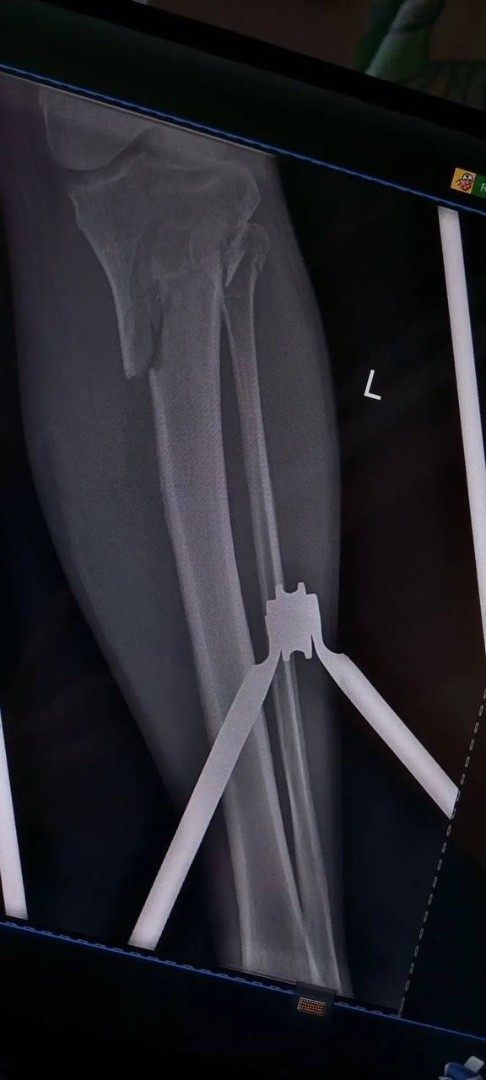

Травматологи горбольницы «Липецк - Мед» почти три часа буквально по кусочкам собирали голени пациента после аварии!

Пациент поступил после тяжелого ДТП 25 февраля с внутрисуставными переломами верхних зон обеих голеней.

Ситуация осложнялась хронической анемией на фоне кровопотери, что требовало особого подхода и скорости.

Заведующий отделением травматологии Дмитрий Соколов с ассистентом, врачом - травматологом Евгением Крюченковым провели одномоментное оперативное  вмешательство на двух конечностях с интраоперационной гемотрансфузией. То есть, оперировали одновременно обе ноги с минимальной кровопотерей.